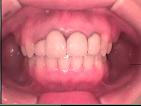

MGS(歯肉整形)

歯周炎に罹りにくくしたり、あるいは審美的要求に応えるため歯肉の整形を行うことがあります。

下のケースでは歯の形や大きさをそろえるため歯肉縁のラインを整える手術をしました。

術前